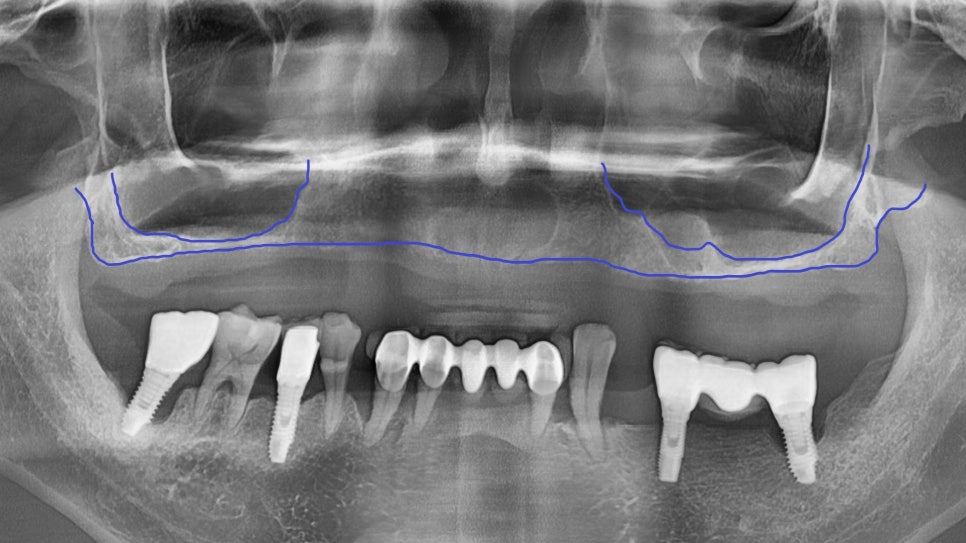

상악동은 위 어금니 바로 위쪽에 위치한

공기주머니 같은 공간으로 얇은 막으로 둘러싸여 있습니다.

사진상에서 보면 이 부위가 상악동인데,

까맣게 보이는 이유는 안이 뻥~ 뚫려 있기 때문이죠.

임플란트를 안정적으로 심으려면

뼈의 높이가 최소 7~8mm는 되어야 합니다.

그런데 이 환자분은 1.5mm밖에 남지 않은 상태였습니다.